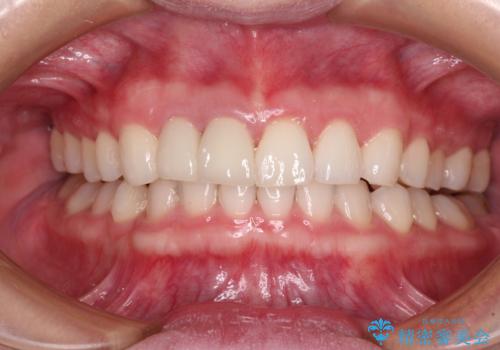

奥歯の咬み合わせを改善しながら、並行してインビザラインで歯列を整えることとしました。

カリエールディスタライザーやワイヤー矯正を併用したことで、確実かつ短期間で治療を終えることができました。